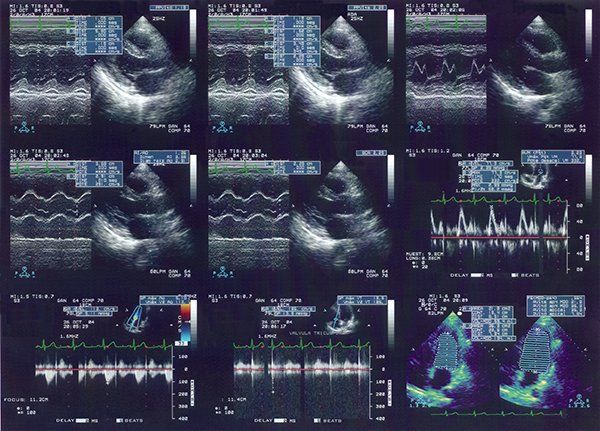

Lo studio Fasano è un punto di riferimento a livello regionale grazie alla sua professionalità e varietà dei servizi offerti: esami ecografici e radiografie del torace, dello scheletro e dell’apparato digerente, nonché le mammografie.

Quando ci si sottopone a esami strumentali, è fondamentale affidarsi a tecnici di laboratorio e medici competenti, oltre ad avvalersi di strumentazioni moderne e macchinari di ultima generazione.